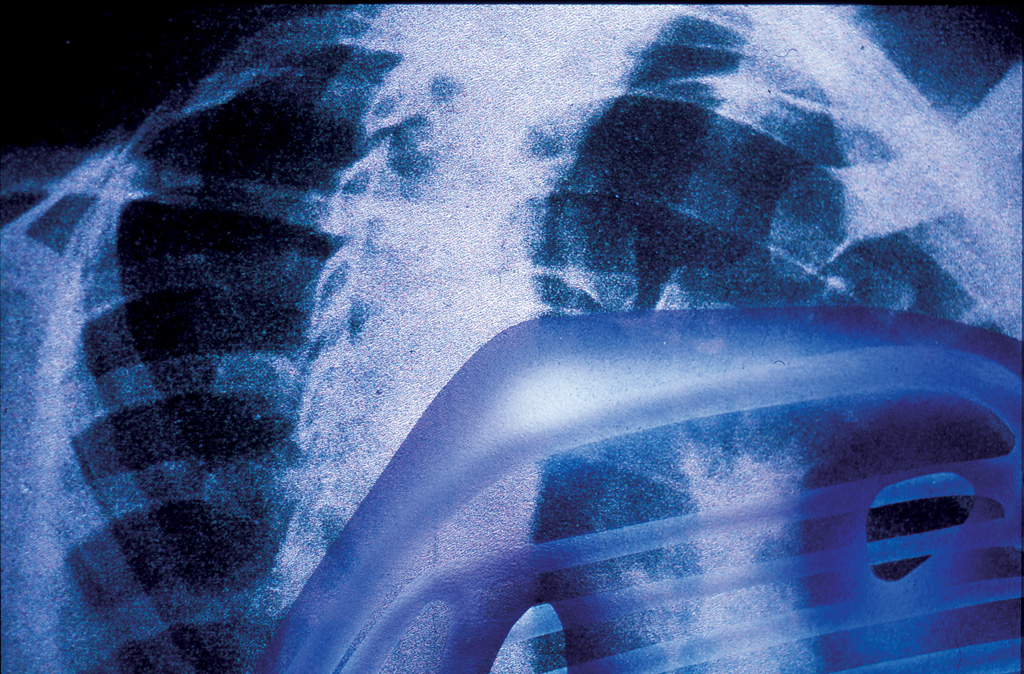

I have just returned to some drawings I made many years ago. I had a request to put them in an exhibition, which might interfere with a couple of other exhibitions that are coming up, so I have made some copies with slight alterations. It is part of the second body project (see here and here) where I altered X-ray photographs of the body and the related positioning photographs to take those X-rays. The positioning pictures (the originals are taken from Positioning in Radiography by K.C. Clark, 1949 edition) have slight bumps on the body that reveal the synthetic organs through formal transparency. I have not altered these much but have developed the X-ray images by spraying transparent cool grey on the interior of the synthetic organs and added soft highlights, which gives a transparency closer to that in an X-ray.

The stereoscopic anatomical drawings describe the apparatus to make an internal architecture. THis sequence of paired drawings discusses the revelation of the architecture in both a practical way but also by implication a sense of the larger spatial consequence of the project. Each pair of drawings has an X-ray and a photographic illustration of the position the body has to hold to take that X-ray. The base images (except for the final X-ray) are taken from Positioning in Radiography by K.C. Clark (1949 edition). Francis Bacon worked from images in the 1939 edition of the same book.

Each X-Ray shows parts of the new body apparatus but they are available to this sort of inspection selectively, so not everything is visible. The positioning photographs display a formal transparency of the apparatus, again selectively as only those parts that press against the skin are visible.

In the positioning picture (2B) you can see a filter under her skin just above her forearm and the top of the breathing/cooling components just below her collar bone, the piece that is visible in the X-ray.

X-Ray 3A is not from Positioning in Radiography, but 3B is, the positioning to take the image in 3A. The X-Ray shows the selective revelation of the intestines through the agency of a barium meal – tissue that would otherwise be transparent to X-Ray shows up due to the meal. The image is unlikely, as the synthetic organs of the new apparatus should divert toxins through the synthetic system (and therefore reveal them more fully) so we have to assume that the apparatus has been turned off to check the natural organs. In the positioning photograph you can again see discrete bumps around her waist and abdomen where the apparatus pushes into the skin.